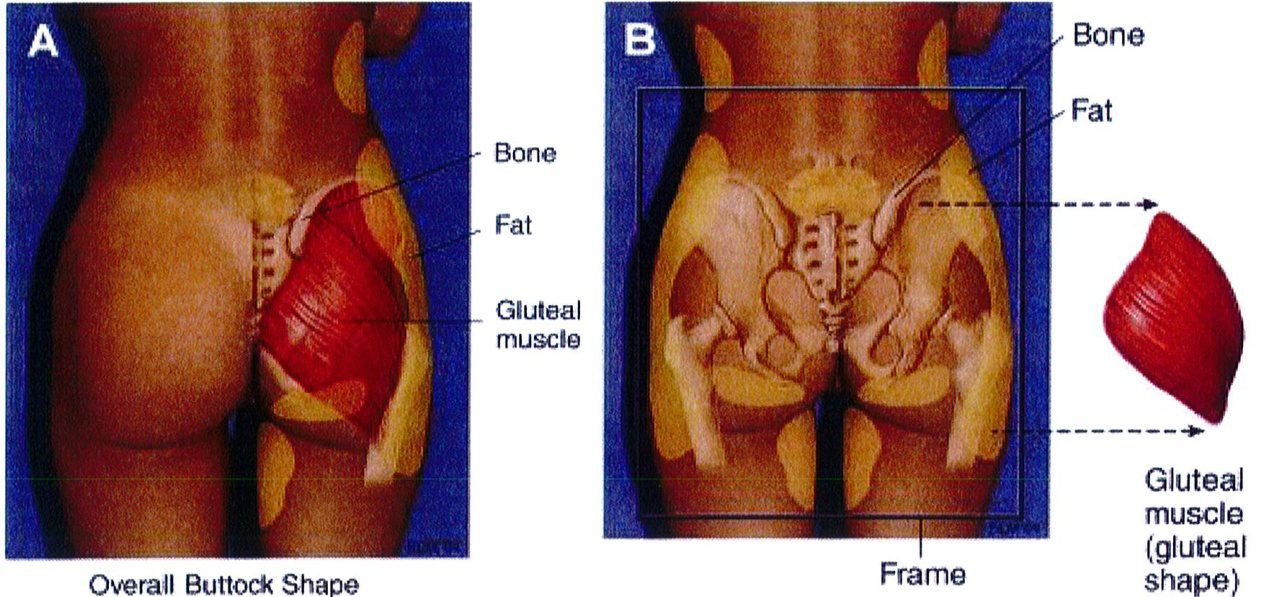

Sự tương tác của 4 tổ chức này mang lại cho vùng mông một hình dáng đặc trưng cụ thế (hình 1A). Để đơn giản hóa chủ đề phức tạp này, hãy tưởng tượng cơ thể là một cấu trúc có thể tháo rời. Khi tách cơ ra thì phần còn lại là khung xương, mỡ và da, có thể gọi chung là khung (Hình 1B).

Hình 1. (A) Hình thể toàn bộ vùng mông phụ thuộc vào khung xương, cơ mông lớn, vị trí và lượng mỡ dưới da, độ căng của da. (B) Khung mông, với cơ môna lớn đã được tách ra.

Over rall Buttock Shape : Hình thể toàn bộ vùng mông Gluteal muscle: Cơ mông Gluateal muscle(gluteal shape): Hình dạng cơ mông Frame: Khung